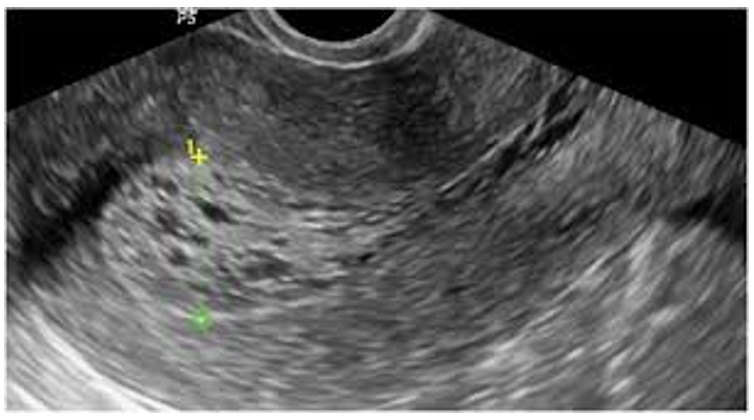

So many “workarounds” it seems regarding the full bladder, and yet, the full bladder is an important part of a transabdominal scan. The full bladder gives a structural landmark that helps orient the imager to the pelvic area. The full bladder pushes the bowel away from the area, allowing for better resolution. A full bladder will also provide what is referred to as a “sonic window”. The sound wave travels through the fluid-filled bladder unimpeded so that when it reaches the uterus, it has a greater intensity than the portion of the sound beam that has traveled through the adjacent soft tissue. This allows for better resolution. Ideally, the bladder should always extend past the fundus of the uterus. Always. The quality of images obtained with a full bladder as opposed to a partially full or completely empty bladder is worth the wait. A full bladder gives the imager a reference for the level of gain necessary for the exam. (This is true as long as the bladder is normal and anechoic)

A possible soft tissue area adjacent to the uterus may appear as a mass without a full bladder. By filling the bladder, if the area is simply bowel, it may move or entirely disappear. The anteverted or anteflexed uterus will be stretched out lengthwise with a full bladder. With an empty bladder, it will remain in one area, making it difficult to thoroughly image the uterus. Sometimes images can be obtained with an empty or partially filled bladder, but too often the payoff of questionable quality images or remaining questions isn’t worth the time that was saved by not filling her bladder. The first question to be asked when evaluating a scan of the uterus will be why the bladder isn’t full. It is standard practice transabdominally.